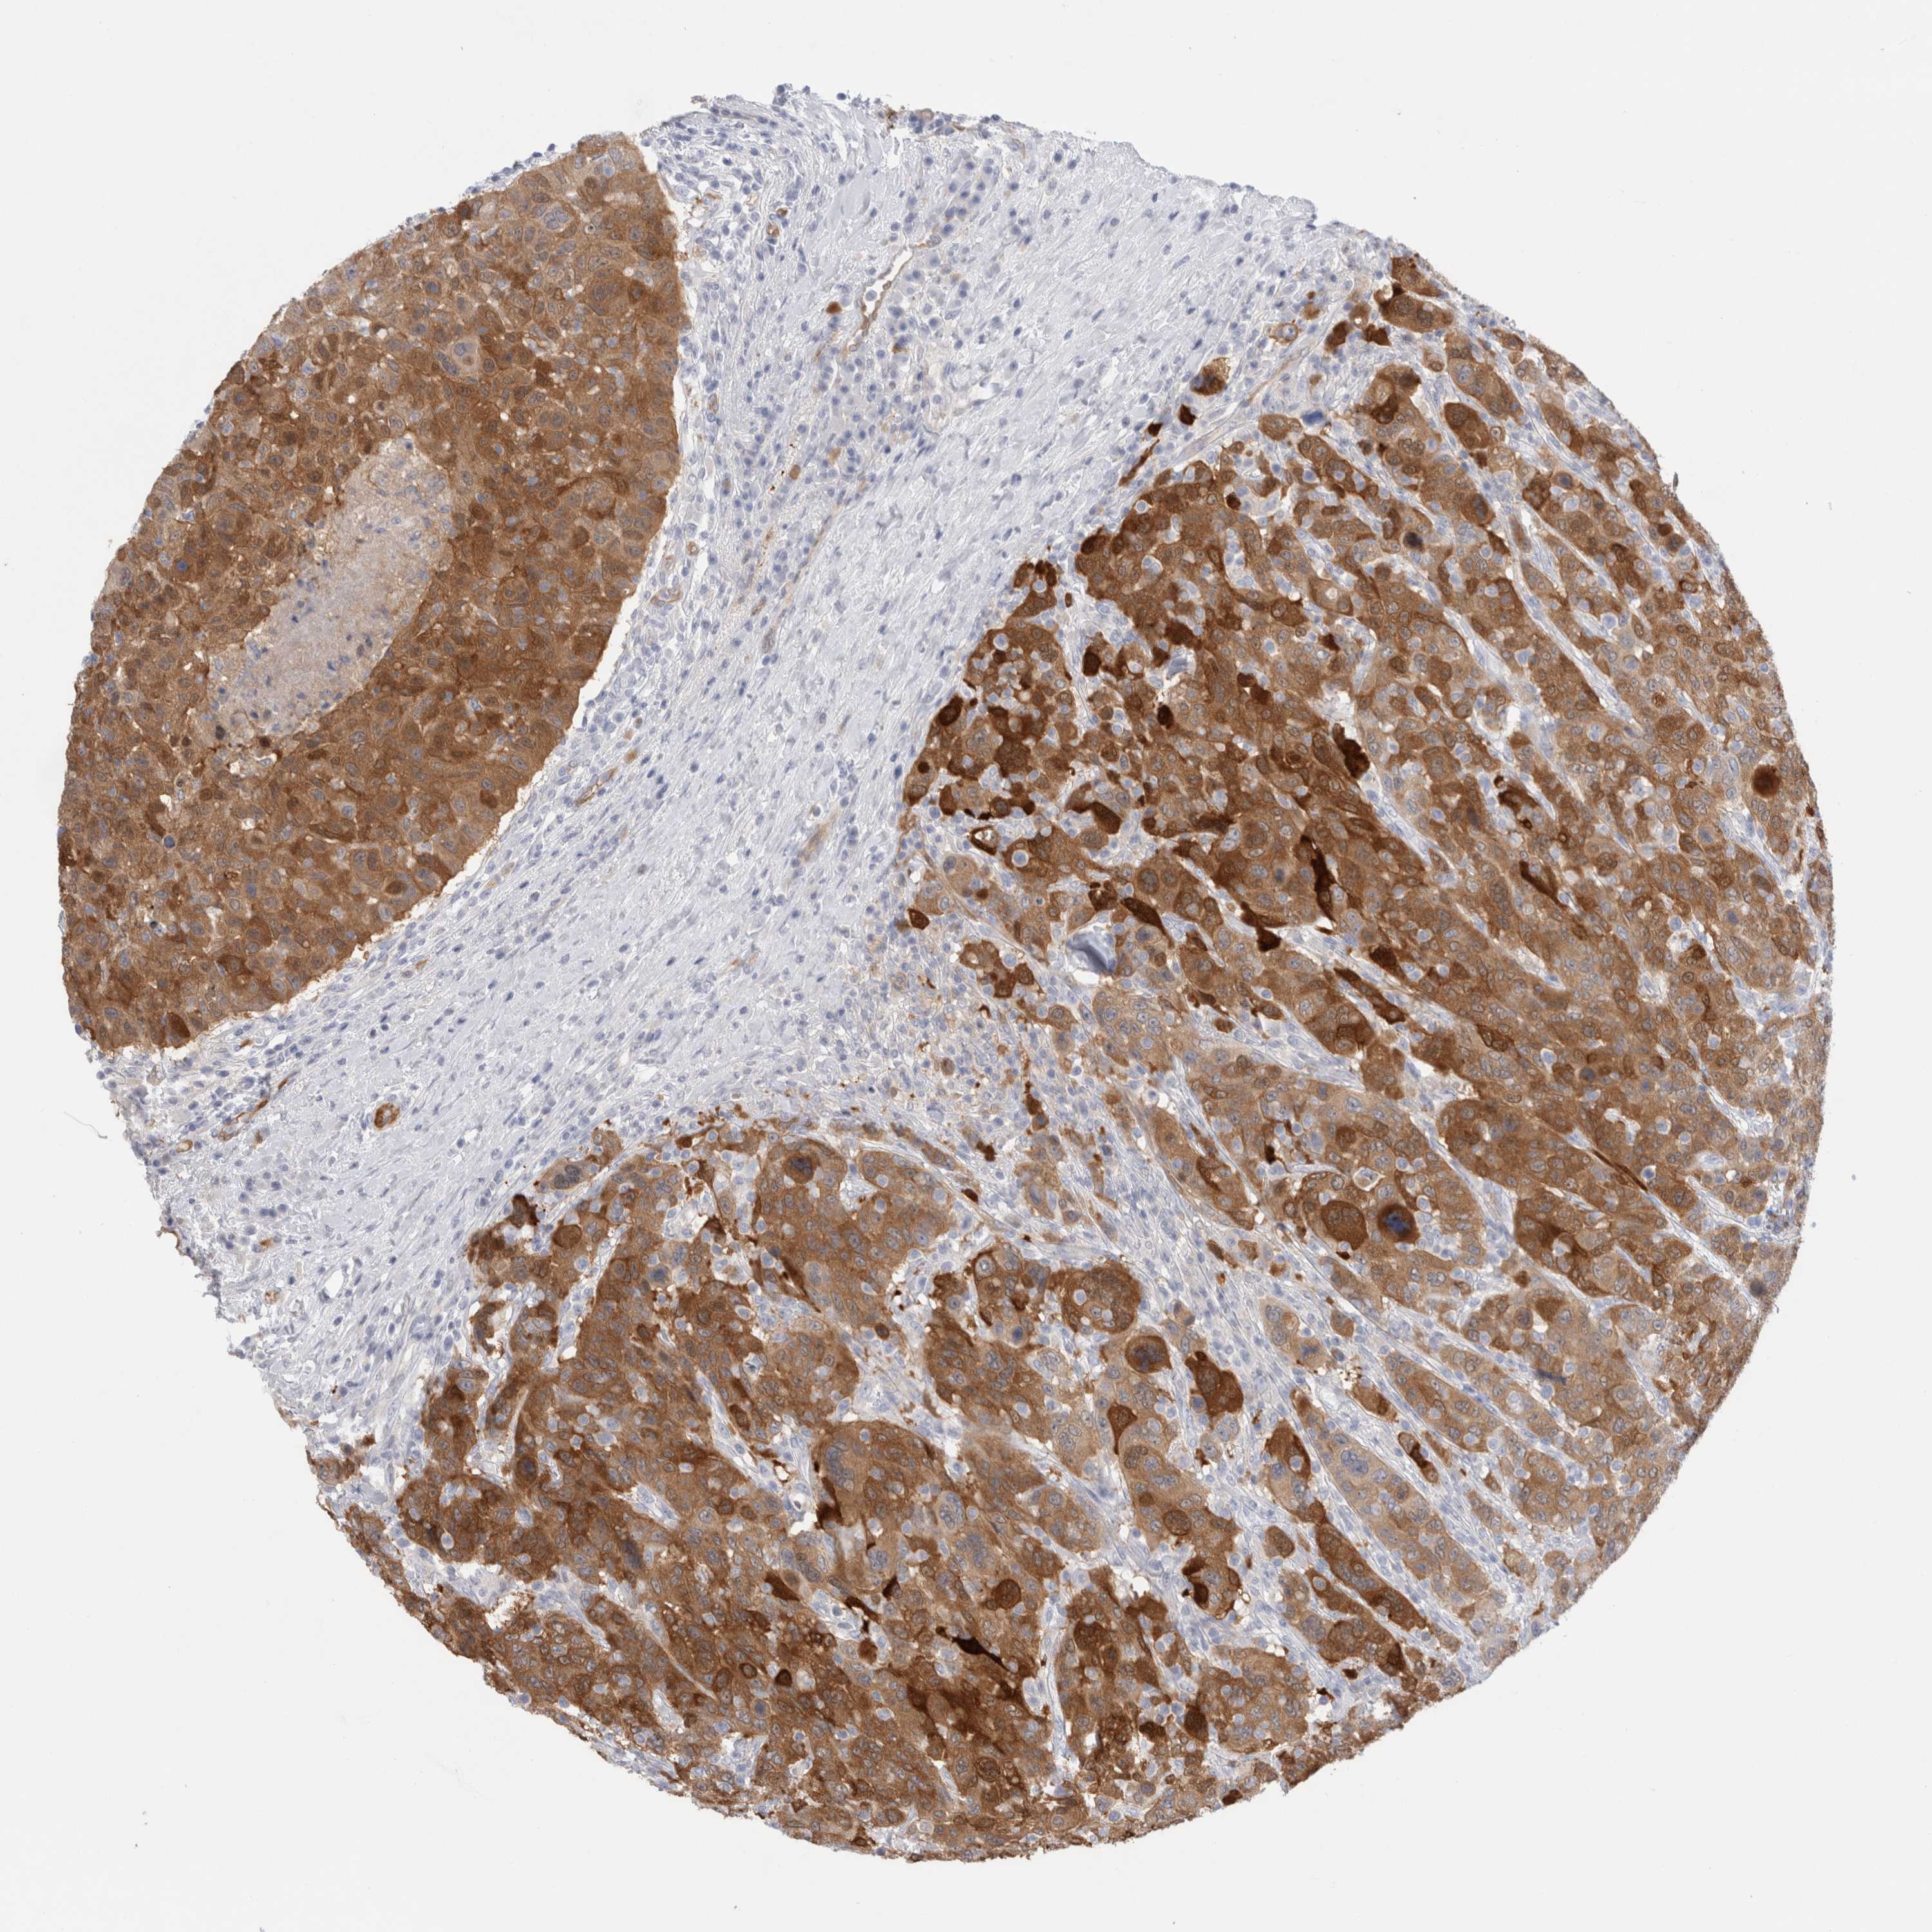

CANCER BREAST CANCER Show tissue menu

BRCA TCGA BRCA VALIDATION PROTEIN EXPRESSION

ANTIBODIES

AND

VALIDATION